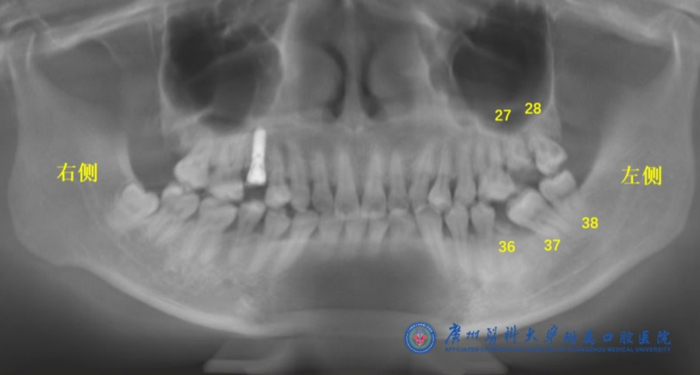

据周丽斌介绍,陈女士的左侧上下颌一共烂了3颗大牙(编号27、28、36),还有2颗严重倾斜的牙齿(编号37、38)(如下图所示)。按照经典的种植修复方案,这5颗牙齿都需要拔掉,然后再种植3颗牙齿(编号27处1颗,编号36和37处2颗)。